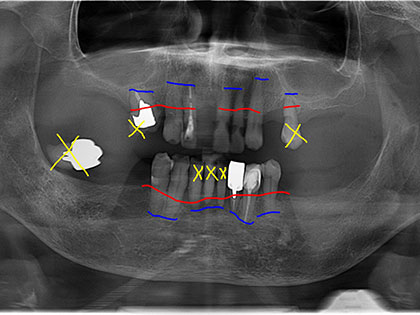

• 全体的に歯周病が進行しており、レントゲン写真をみますと青い線が根の先、赤い線が歯を支えている骨のある位置です。黄色の×は抜歯した歯です。

• 今までと同様なバネを残っている歯にかけると、残っている歯が更にグラグラして、最終的には自分の歯が痛みが強くなり抜歯になります。

• それであれば歯の神経を取り、その上にマグネット(磁石)を装着した方が根の寿命も延びますし、バネで揺れ動き入れ歯がすれて歯肉が痛くなることも少なくなります。

• 今回、極端に悪い歯は抜きました。

• 今回は上下に5か所ずつマグネットを装着し、その上に金属床義歯を上下にセットしました。